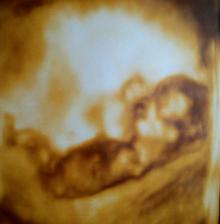

Tak to vše začalo.....